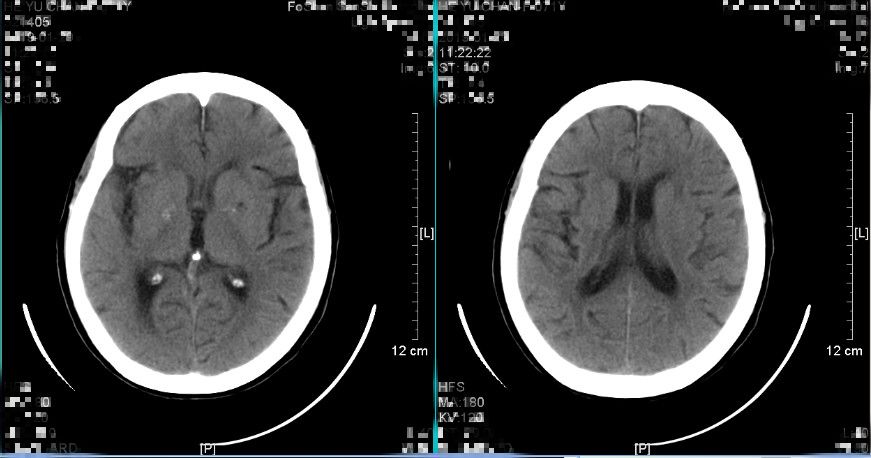

图1. 入院前急诊查头颅CT提示:1.右侧额颞顶部硬膜下血肿,中线略向左移位2.考虑少量蛛网膜下腔出血(2018-12-21 12:53)

患者入院时受伤程度轻,无昏迷,GCS评分15分,提示脑挫伤轻微;入院时头颅CT提示沿硬膜下间隙分布的窄弧带样高密度影,呈断线样高低密度混杂影,中线结构向左偏移约0.5cm,最大血肿厚度约0.8cm,基底池无受压,血肿多位于侧裂附近额顶部,且患者为老年女性,脑萎缩提供了一定的代偿空间,综合考虑此病例为“早期快速自然消散”的特殊类型急性创伤性硬膜下血肿。详细与患者及其家属讲解病情后,采取保守治疗观察方案,密切观察生命体征变化,保持呼吸道通畅,密切观察神经系统体征,给予止血、维持水电解质平衡、控制血压等对症支持处理,未予脱水药物处理,拟伤后12小时再次复查头颅CT检查。

图4. 伤后约10小时复查头颅CT提示:硬膜下血肿较前减少消散,以低密度血肿减少为主,中线结构偏移程度减轻。(2018-12-21 20:16)

患者入院后仍保持清醒状态,头痛等症状无继续加重,根据复查头颅CT检查提示硬膜下血肿较前减少,最大血肿厚度约0.5cm,中线向左偏移约0.3cm,提示此病例为“早期快速自然消散”的特殊类型急性创伤性硬膜下血肿,继续予保守治疗观察。